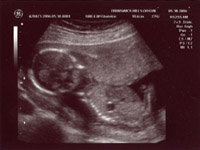

| June 28, 2006 - Twenty Week Ultrasound: IT'S A BOY!!! |

Today was probably the

longest day of my life having to wait for our 3:00pm appointment. I

went to work today, but didn't get much done since I was so excited to

finally find out what we were having. We got to the doctor's and they

took us right away. Within 44 seconds of the technician turning on the

ultrasound machine, she showed us the picture of the legs spread wide open

and it was obvious that we were having a boy!! He was so active

throughout the entire ultrasound, kicking and turning all over the place.

He is absolutely beautiful!!! I am in love with him already. He

weighed 13.5 ounces and he is perfect and healthy!! We are so excited

to start planning the nursery for our little man. Here are the

ultrasound pics from today. Enjoy!! ~Jen

View from the backside |